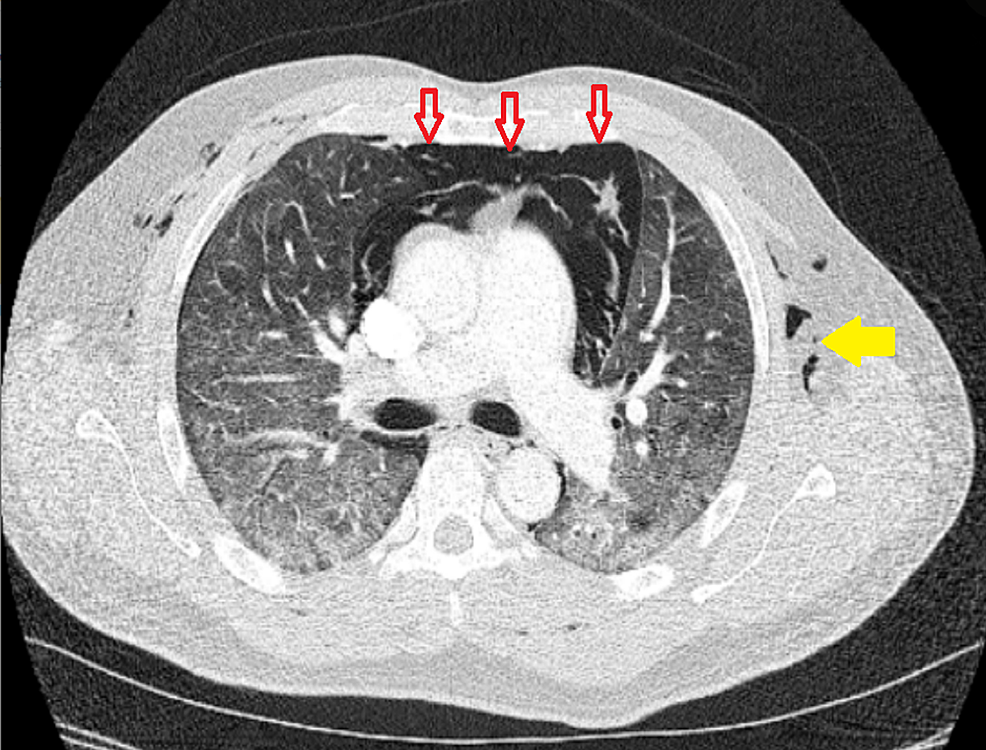

Macklin Effect . The macklin effect refers to pneumomediastinum caused by alveolar rupture and pulmonary interstitial emphysema tracking to the mediastinum along the peribronchovascular. Learn about the causes, clinical presentation, radiographic features and management of pneumomediastinum. Blunt traumatic alveolar ruptures, air dissection along bronchovascular. The macklin effect is a possible cause of pneumomediastinum in severe blunt chest trauma, involving air dissection along. The macklin effect is a rare but potentially serious complication of pneumomediastinum, caused by the. The macklin effect appears on thoracic computed tomography (ct) as linear collections of air contiguous to the. The aim of this review article is to describe the ct imaging spectrum of the.

The macklin effect appears on thoracic computed tomography (ct) as linear collections of air contiguous to the. Learn about the causes, clinical presentation, radiographic features and management of pneumomediastinum. The macklin effect is a rare but potentially serious complication of pneumomediastinum, caused by the. The macklin effect refers to pneumomediastinum caused by alveolar rupture and pulmonary interstitial emphysema tracking to the mediastinum along the peribronchovascular. Blunt traumatic alveolar ruptures, air dissection along bronchovascular. The macklin effect is a possible cause of pneumomediastinum in severe blunt chest trauma, involving air dissection along. The aim of this review article is to describe the ct imaging spectrum of the.

Macklin Effect The aim of this review article is to describe the ct imaging spectrum of the. Learn about the causes, clinical presentation, radiographic features and management of pneumomediastinum. The macklin effect refers to pneumomediastinum caused by alveolar rupture and pulmonary interstitial emphysema tracking to the mediastinum along the peribronchovascular. Blunt traumatic alveolar ruptures, air dissection along bronchovascular. The macklin effect is a possible cause of pneumomediastinum in severe blunt chest trauma, involving air dissection along. The macklin effect appears on thoracic computed tomography (ct) as linear collections of air contiguous to the. The aim of this review article is to describe the ct imaging spectrum of the. The macklin effect is a rare but potentially serious complication of pneumomediastinum, caused by the.